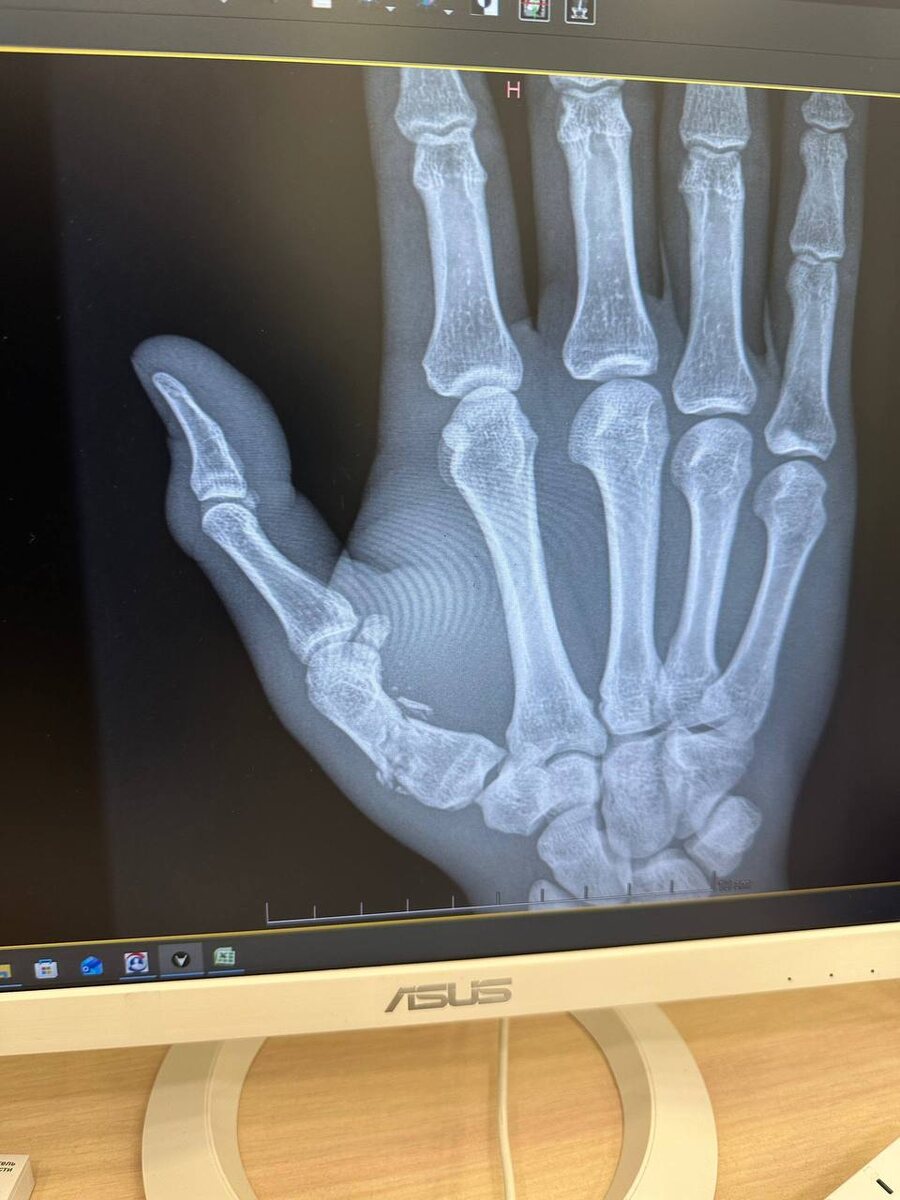

Читинский боец UFC Андрей Пуляев сломал кисть во время боя с камерунцем Атеба Готье на турнире UFC 324. Пуляев показал рентгеновский снимок в своем тг-канале.

Секундант бойца Андрей Корешков ранее говорил, что Пуляев сломал большой палец уже в первом раунде:

По сути, во второй и третьей пятиминутках бился с переломом и неплохо попадал.

Фото из тг-канала Андрея Пуляева